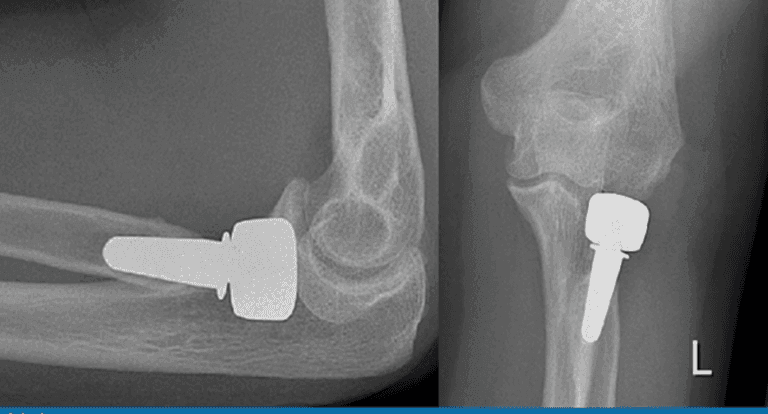

| Radial head | Radial head replacement | Figure 1 |

| Humeroradial | Radial head replacement | Figure 1 |

| Radioulnar | Radial head replacement Figure 1 |